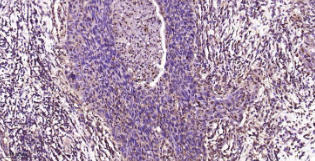

Immunohistochemical analysis of paraffin embedded human cervical cancer tissue slide using IHC0448H (Human PSMA2 IHC Kit).